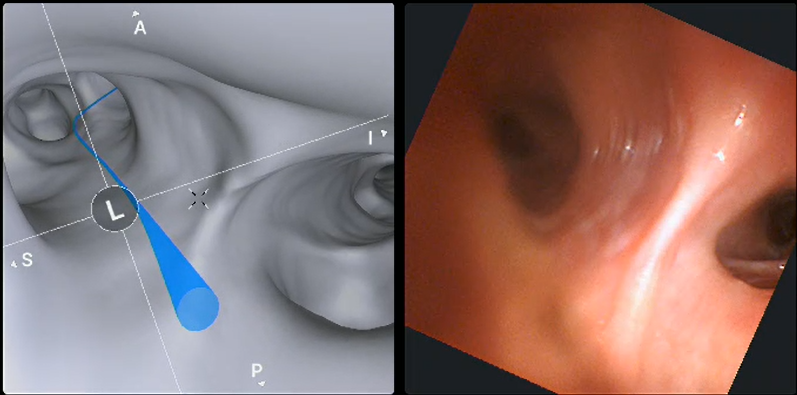

The Ion system creates a 3D roadmap of your airways and lungs, highlighting the tumours within each lung that need to be biopsied. The roadmap helps the clinician to navigate your airways and see exactly where each tumour is – similarly to a car satnav mapping out a route to follow.

3D roadmap of the lungs with the suggested access routes to the tumour shown by the blue line.

Once you are under anaesthesia, the Ion catheter with the camera on the end will be inserted via your mouth, and carefully guided down your airways into your lungs. As it travels down, the Ion’s active robotic system uses shape-sensing technology to navigate and update the 3D roadmap, showing the clinician operating the machine exactly where the tumour is within the lung. The highly specialised CT scanner located in the procedural suite is then used in addition to determine the exact location of the target nodule, and to confirm the collection of very precise biopsies.

The Ion 3D roadmap to guide accurate lung biopsy and surgery.